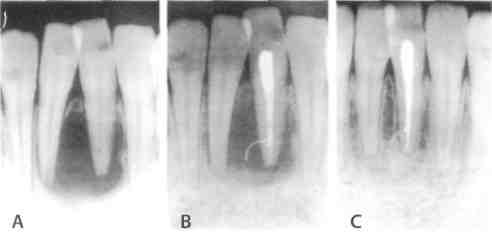

Рентгенография небного шва: Медицинские исследования и диагностика